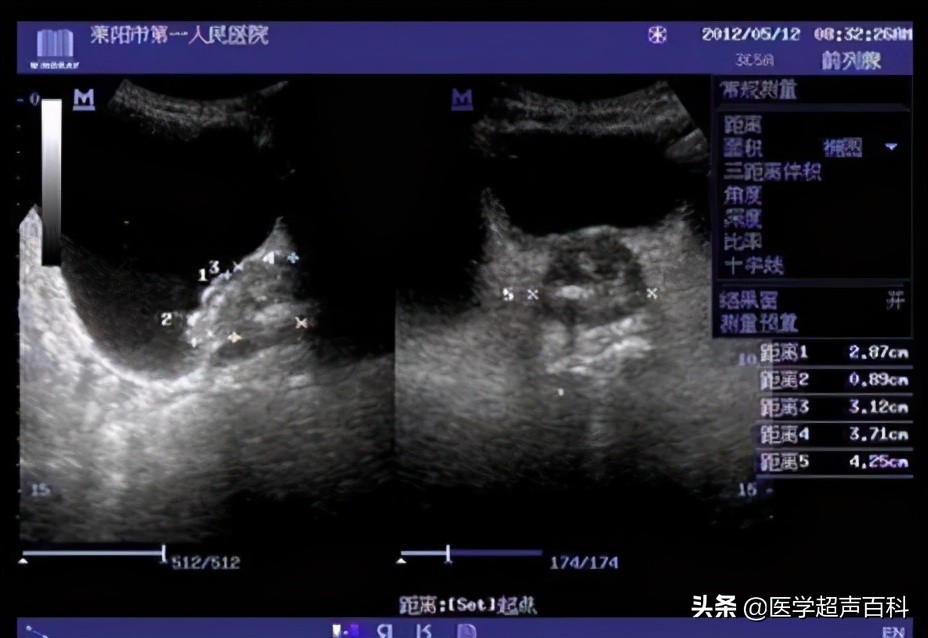

膀胱肿瘤的B超表现

膀胱壁可见菜花样、乳头状或团状中、强回声凸向膀胱,表面粗糙、不光滑,不随体位移动。

肿瘤多有瘤蒂与膀胱粘膜相连,连接处膀胱壁回声模糊,连续性中断,肿瘤基底部常较宽,膀胱壁局限性增厚。

CDFI:显示肿瘤基底部有细条状血流,多普勒频谱显示动脉频谱:RI〉0.60。